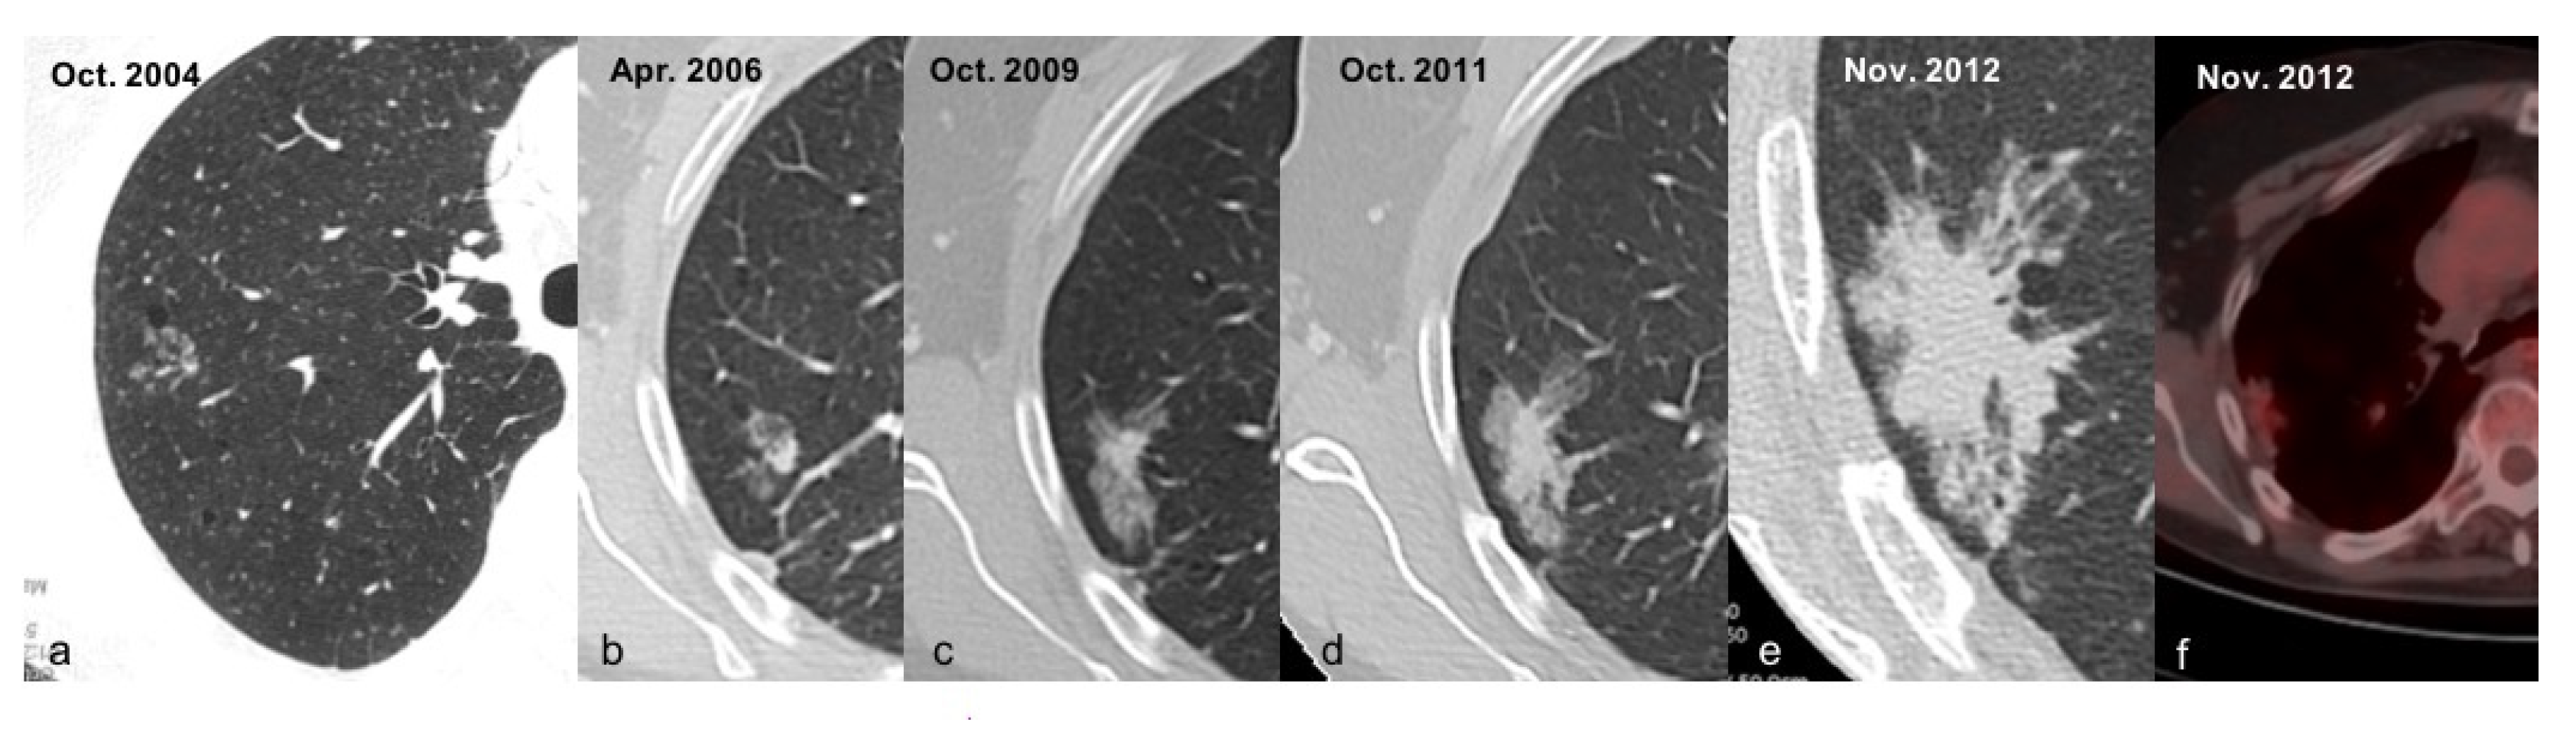

- Volterrani, L.; Guerrini, S.; Zanfrini, E.; Grassi, A.; Addamo, E.; Mathieu, F.; Gentili, F.; Bellan, C.; Spina, D.; Mazzei, M.A.; et al. HRCT predictors of GGO surgical resection: Histopathological and molecular correlation in the era of lung sparing surgery. Lung Cancer 2022. [Google Scholar] [CrossRef]